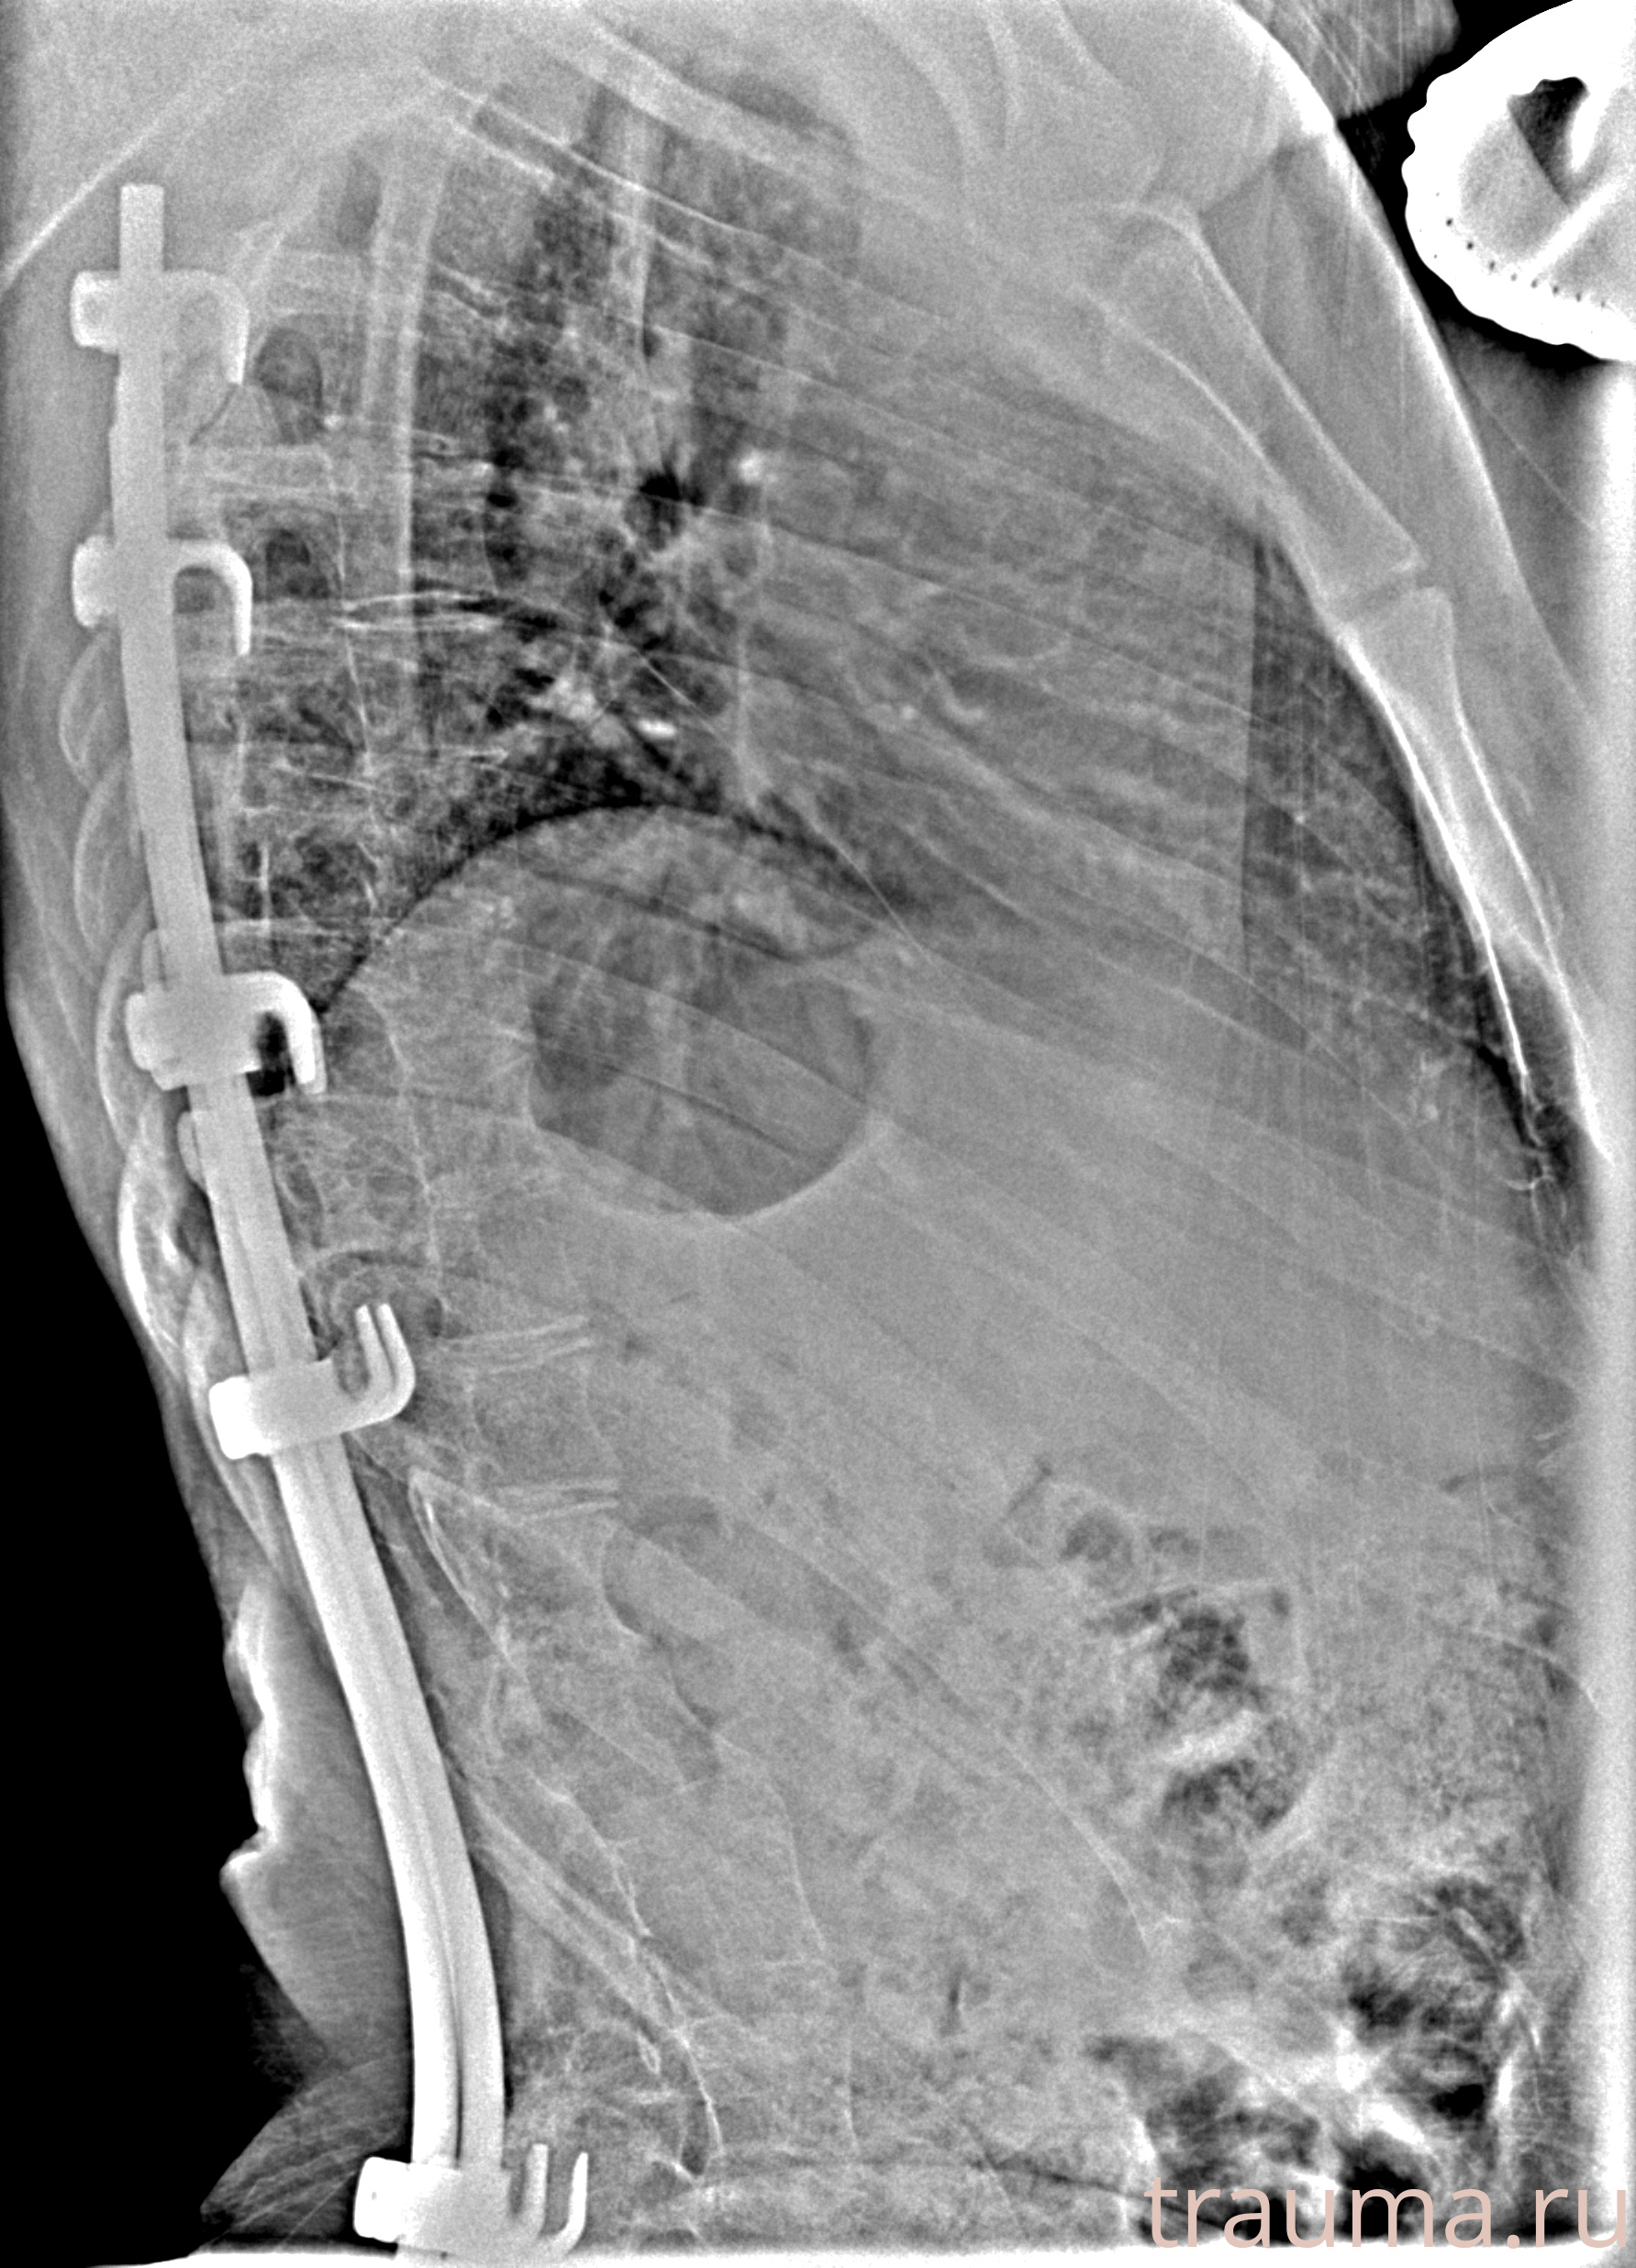

Рентгенограммы

Рентген на дому: по вашему адресу приезжает врач-рентгенолог, травматолог-ортопед с мобильным рентгеновским аппаратом, проводит диагностику травмы или заболевания, делает необходимые рентгенограммы, дает рекомендации по дальнейшему лечению. Получить качественные снимки в домашних условиях возможно благодаря уникальной методике, разработанной МосРентген Центром для института  Склифосовского